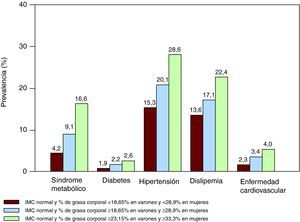

Obesidad con peso normalAlgunos informes recientes indican que los individuos con peso corporal normal definidos por IMC podrían estar en riesgo de sufrir síndrome metabólico, alteraciones cardiometabólicas e incluso mayor mortalidad. Un estudio reciente ha demostrado que los varones con peso normal en el tercil superior de porcentaje de grasa corporal (> 23% de grasa corporal) tienen 4 veces más probabilidades de presentar síndrome metabólico y tenían mayor prevalencia de diabetes mellitus, hipertensión arterial, dislipemia y enfermedad cardiovascular que aquellos en el tercil inferior. Las mujeres en el tercil más alto de grasa corporal (> 33% de grasa corporal) tienen 7 veces más posibilidades de presentar síndrome metabólico (Figura 4). Curiosamente, las mujeres con obesidad y peso normal tienen casi 2 veces más probabilidades de morir en el seguimiento que las mujeres en el tercil más bajo de grasa corporal84. Aunque se requiere de más estudios para confirmar estos resultados, está claro que los individuos con peso normal basado en IMC podrían necesitar una clasificación más detallada para definir mejor su riesgo cardiometabólico relacionado con su adiposidad.

Figura 4. Prevalencia de síndrome metabólico, factores de riesgo e historia de enfermedad cardiovascular en individuos con peso normal según terciles de grasa corporal. Los sujetos en el tercil más alto (verde) serían los denominados obesos con peso normal 77 . IMC: índice de masa corporal.